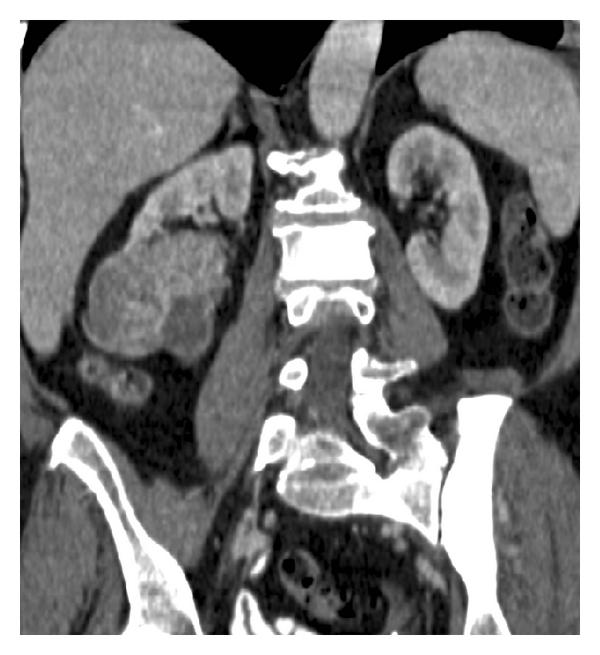

Ultrasound plays an important role in the detection and evaluation of these SRMs. While this technique may not be as sensitive as contrast-enhanced CT or MR for revealing SRM, US has been the initial technique in the discovery of a large number of these incidentally discovered tumors when the kidney is studied in the course of abdominal imaging. Sonography is very accurate in distinguishing liquid from solid tissue. Therefore, its major use in these small lesions is to help differentiate small cysts (see Figure 1) from small solid tumors [8]. Maintaining rigid criteria is necessary to maintain the high accuracy possible with this technique.

In the general population, renal cysts are the most common space-occupying lesions in the kidney. With this technique, 80% of detected renal masses are characterized as simple cysts [9] thus ending their diagnostic evaluation. The remaining 20% of renal masses require further study with CT or MR imaging [10]. Any mass detected that does not meet the strict sonographic criteria for a simple cyst should be further evaluated with CT or MR imaging of the kidneys. However, one or two thin septations may also be visible sonographically in simple renal cysts [11]. Because these findings are diagnostic, no further imaging or followup is needed in the evaluation of these lesions. However, other atypical features sonographically detected calcifications; more than two septations, septal thickening or nodularity, and the presence of solid components indicate that sonography alone will not be adequate for complete evaluation of these renal masses (see Figure 2). The addition of Doppler sonography, color Doppler sonography, power Doppler sonography [12, 13], and sonographic contrast agents may further improve the detection and characterization of renal masses. However, none of these techniques preclude the need for CT or MR imaging of renal masses that do not meet the sonographic criteria for diagnosis of a simple cyst.